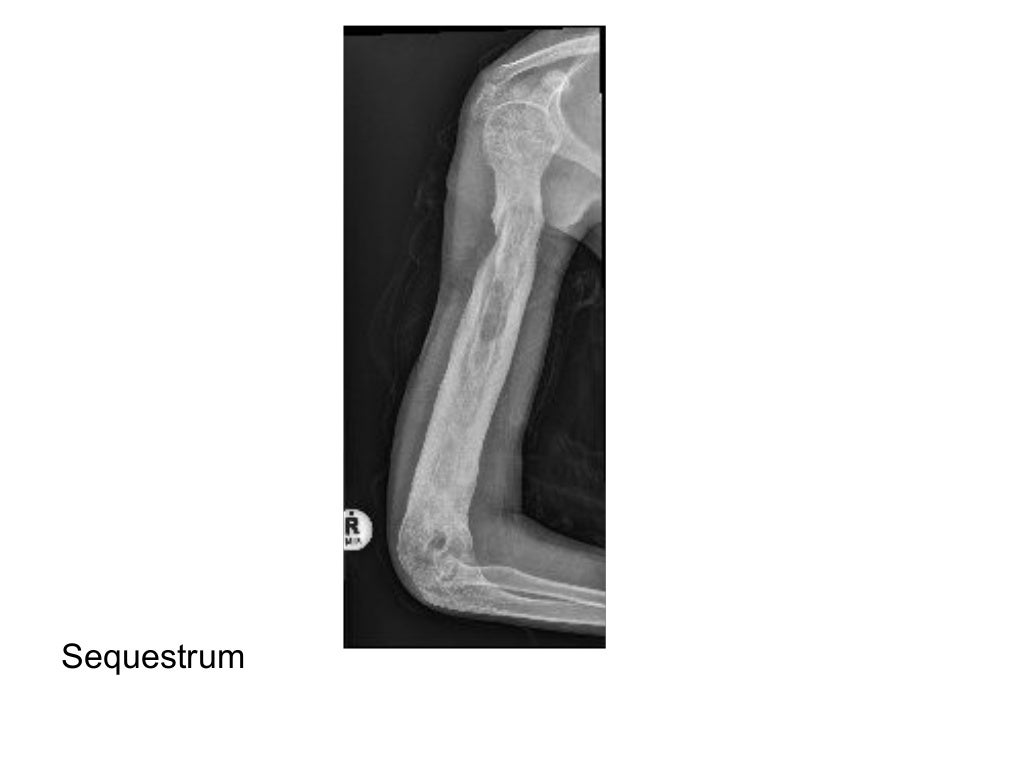

BONE INFECTION MIMICKING BONE TUMORS HOW TO MAKE Lab Tests Infection Of Bone A complete blood count (cbc) is useful for evaluating leukocytosis and anemia. It can be very serious and cause permanent. Doctors may use blood tests to determine whether you have an infection. Osteomyelitis is an infection in a bone. Leukocytosis is common in acute osteomyelitis before therapy. Findings include erythema, soft tissue infection, bony tenderness, joint effusion, decreased range of. Lab Tests Infection Of Bone.